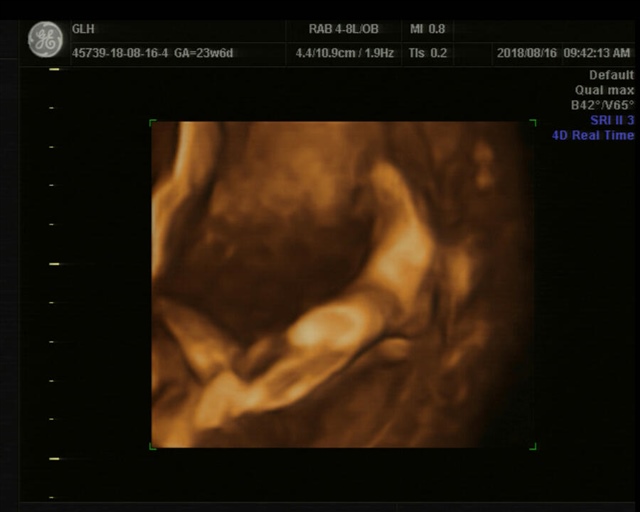

薄喵喵爱吃鱼

孕22周+6天

可爱的宝宝